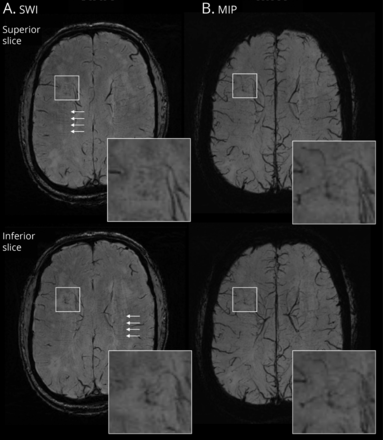

代表vessel-cluster连续出现在轴向片零星的小血管疾病患者。vessel-cluster(广场)2所示连续轴向片(优越伪劣)susceptibility-weighted成像(瑞士,)和最大强度投影(MIP, B)序列。增强的vessel-cluster地区,小血管清晰可见点的外观可追踪的连续切片或MIP序列增强这些结构通过不同飞机的可见性。注意到大部分的船只从集群收敛于静脉深静脉系统,但这些血管的分布是无序的,不同于正常平行的外观深髓小静脉中可见椎体semiovale(白色箭头)。

为每个vessel-cluster(每个集群分析),我们评估表格大小vessel-cluster体积和同心壳在周围组织。表格大小vessel-cluster卷于73年提供的94(76%)与表格除coregistered很差的小卷后地图,和扩大销量和界限不明的壳(93/94的患者中,99%)。在vessel-cluster卷(包括卷4-voxel扩张)对应于完整的蛀牙,表格级较低较侧卷(2-sample学生t测试)。这些vessel-clusters周围白质(4-voxel壳)表格与镜像卷相比也较低。这些差异在表格大小没有显著vessel-cluster卷对应部分或没有空泡(图5eTable 4links.lww.com/WNL/C29)。

森林情节分析36 vessel-clusters完全空化(A)和57 vessel-clusters没有完整空化(B)黑色点(vessel-cluster卷)和灰色方块(侧卷)代表的意思是脑血管反应性(表格),和酒吧代表SD。*代表一定的意义(p)2-samplet测试< 0.05。在左边的面板中,图表代表表格在vessel-clusters同心扩张(包括),在右边的面板中,原始集群内的图表表示表格独立和同心壳。

最后,在群vessel-clusters完整空化,有显著线性梯度增加表格的大小值vessel-cluster体积通过同心界限不明的壳(对比0.015,95%可信区间0.007 - -0.023,z = 3.91,p< 0.001),但这个梯度不是出现在集群没有完整的蛀牙(对比−0.002,95%可信区间-0.008到0.005,z =−0.49,p= 0.624),交互p< 0.001 (eFigure 6,links.lww.com/WNL/C29)。